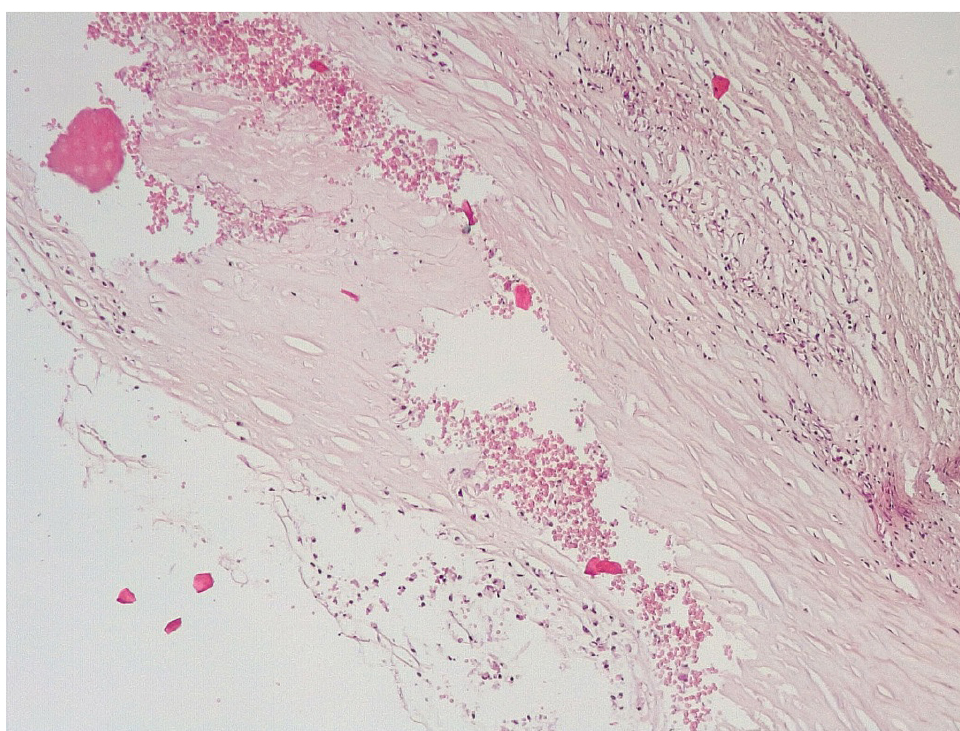

Позднее, спустя 3–7 суток после стентирования КА в просветах имелись пристеночные смешанные фибриново-лейкоцитарные тромбы, которые могли служить источником развития тромбоэмболических осложнений мелких дистальных ветвей коронарного кровотока и развитием острого инфаркта миокарда (рис. 4).

Маркер эндотелиальной дисфункции – фактор Виллебранда (ФВ) ярко экспрессировался в клетках эндотелия КА и субинтимально, что могло свидетельствовать о выраженной дисрегуляции коагуляционных свойств крови (рис. 5). В то же время экспрессия белка CD31 в указанные сроки после стентирования была слабовыраженной, что могло указывать на выраженные дистрофические изменения эндотелиальных клеток КА.